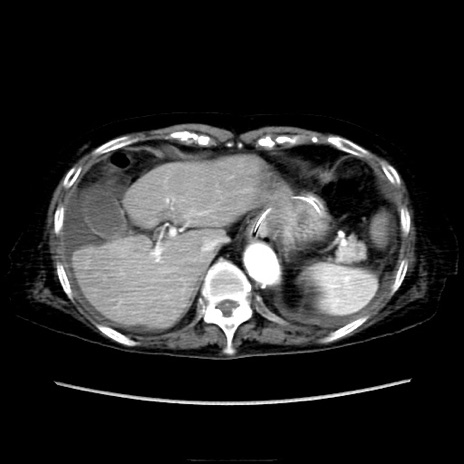

症例40(横断像)

【症例】90歳代女性

【主訴】腹痛・嘔吐

【現病歴】 食欲低下、嘔吐があり昨日他院受診。肺炎と診断され入院となる。入院後より腹部全体に圧痛あり。胃管留置され経過みていたが、症状持続するため、

当院転院となる。

【既往歴】胸椎圧迫骨折、胆石症

【身体所見】腹部:中央に激痛あり、圧痛あり、反跳痛不明

【データ】WBC 17100、CRP 18.82

他院CT

横断像